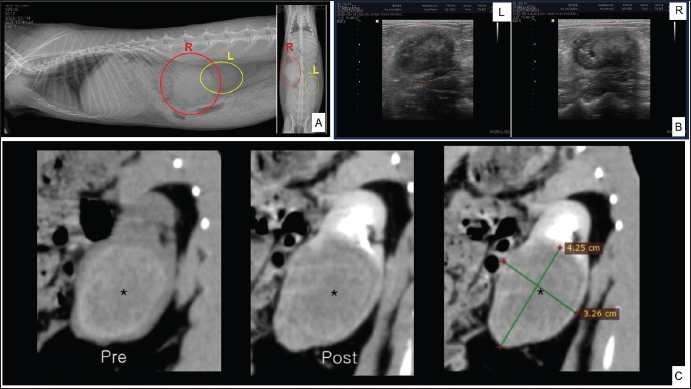

A 4.5-year-old castrated male Lionhead rabbit with a history of poor appetite and abdominal distension was admitted to an animal hospital. The complete blood count and blood chemistry test results suggested mild dehydration. The complete blood count also revealed leukocytopenia with lymphocytopenia and high hematocrit levels. Abnormal serum biochemistry findings included hyperglycemia, hyperproteinemia, hyperglobulinemia, and hypocholesterolemia. In contrast, blood urea nitrogen (BUN), creatinine, BUN/creatinine ratio, and other profiles were normal. We performed radiography (X-rays), ultrasound, and computed tomography, which revealed a significantly enlarged right kidney (Fig. 1A) with a mass-like area (Fig. 1B). A contrast media agent was intravenously injected into the mass; the mass measured 4.25 × 3.26 cm with calcification originating from a suspected area in the right kidney. There was no contrast enhancement, suggestive of a benign lesion such as an abscess or granuloma (Fig. 1C). The right kidney was removed and organ enlargement was confirmed (Fig. 2A). The obtained kidney was fixed in 10% neutral-buffered formalin. When sectioned, a firm yellowish mass within the parenchyma with loss of the cortex and medulla extending towards the capsule was observed (Fig. 2B). The mass was trimmed and stained with hematoxylin and eosin (H&E) for routine histopathological examination.

Fig. 1. Diagnostic imaging tests. Lateral (left) and ventrodorsal (right) abdominal radiographic findings in the rabbit (A). Ultrasonographic results of the left (L) and right (R) kidneys (B). computerized tomography (CT) scan comparing the pre- and post-stain injection and measuring the suspected abscess area of the right kidney (C).